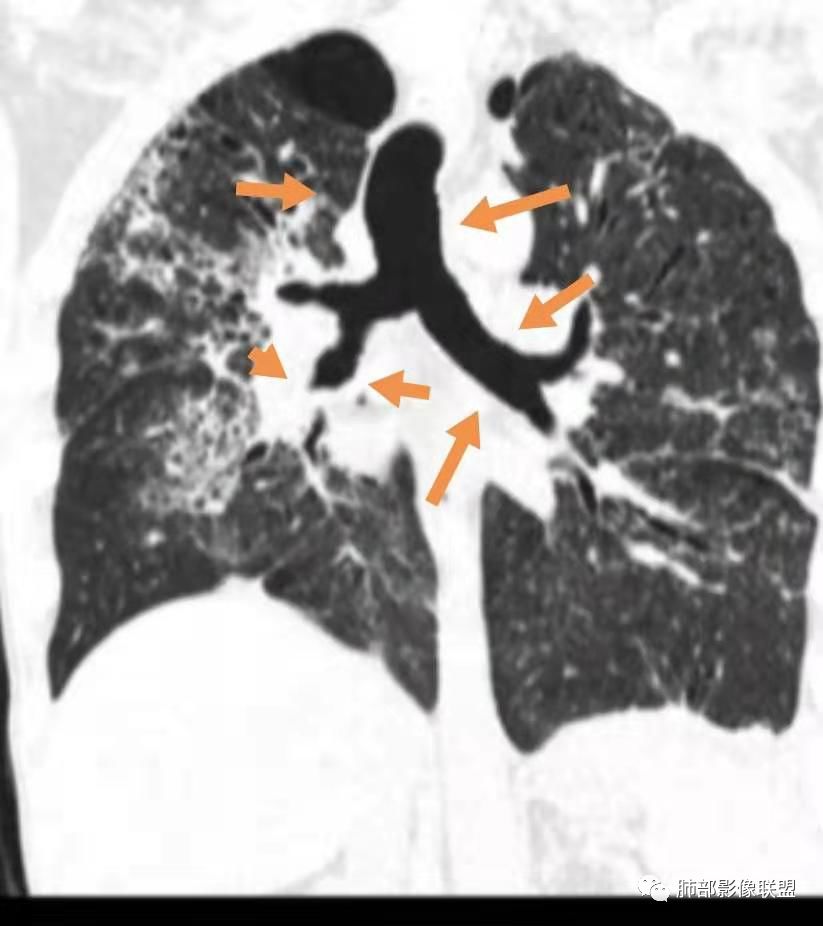

中央间质指的是这吗?

对,大的支气管血管周围

胸部CT:两肺弥漫病灶,中央间质分布为主,部分位于胸膜及叶间裂旁,磨玻璃影,斑片影,部分实性结节,肺气囊,支气管血管束增粗,小叶间隔增厚,叶间裂不均匀增厚,支气管走形有扭曲扩张,可见纤维化、气肿、大泡。考虑:LIP加MALT。鉴别PLCH、PCP、结核、结缔组织病肺浸润。

两肺弥漫病灶,中央间质分布为主,部分位于胸膜及叶间裂旁,磨玻璃影,斑片影,部分实性结节,肺气囊,支气管血管束增粗,小叶间隔增厚,叶间裂不均匀增厚。考虑:间质性肺病,LIP,鉴别OP

病变一般沿血管支气管束分布或小叶分布,一般上肺多于下肺(这与常见继发性肺结核分布相若)。

2. 肺气肿背景(小叶中心性肺气肿);双肺多发病灶整体沿血管支气管束及胸膜下分布,以上叶及下叶背段分布为主,有实变及GGO,边界清楚,有树芽,小叶间隔及中央间质增厚,叶间裂见到多发结节,部分支气管不规则牵拉扩张,提示病灶纤维化明显,结合临床病史,考虑病灶为间质性感染,肺门及纵隔内有钙化淋巴结,小叶间隔结节,考虑淋巴道增值性疾病可能,综合常规要怀疑间质性肺结核。